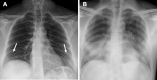

Purpose: The aims of our study are: (1) to estimate admission chest X-ray (CXR) accuracy during the descending phase of pandemic; (2) to identify specific CXR findings strictly associated with COVID-19 infection; and (3) to correlate lung involvement of admission CXR with patients' outcome.

Materials and methods: We prospectively evaluated the admission CXR of 327 patients accessed to our institute during the Italian pandemic descending phase (April 2020). For each CXR were searched ground glass opacification (GGO), consolidation (CO), reticular-nodular opacities (RNO), nodules, excavations, pneumothorax, pleural effusion, vascular congestion and cardiac enlargement. For lung alterations was defined the predominance (upper or basal, focal or diffuse, central or peripheric, etc.). Then radiologists assessed whether CXRs were suggestive or not for COVID-19 infection. For COVID-19 patients, a prognostic score was applied and correlated with the patients' outcome.

Results: CXR showed 83% of specificity and 60% of sensitivity. GGO, CO, RNO and a peripheric, diffuse and basal prevalence showed good correlation with COVID-19 diagnosis. A logistic regression analysis pointed out GGO and a basal or diffuse distribution as independent predictors of COVID-19 diagnosis. The prognostic score showed good correlation with the patients' outcome.

Conclusion: In our study, admission CXR showed a fair specificity and a good correlation with patients' outcome. GGO and others CXR findings showed a good correlation with COVID-19 diagnosis; besides GGO a diffuse or bibasal distribution resulted in independent variables highly suggestive for COVID-19 infection thus enabling radiologists to signal to clinicians radiologically suspect patients during the pandemic descending phase.